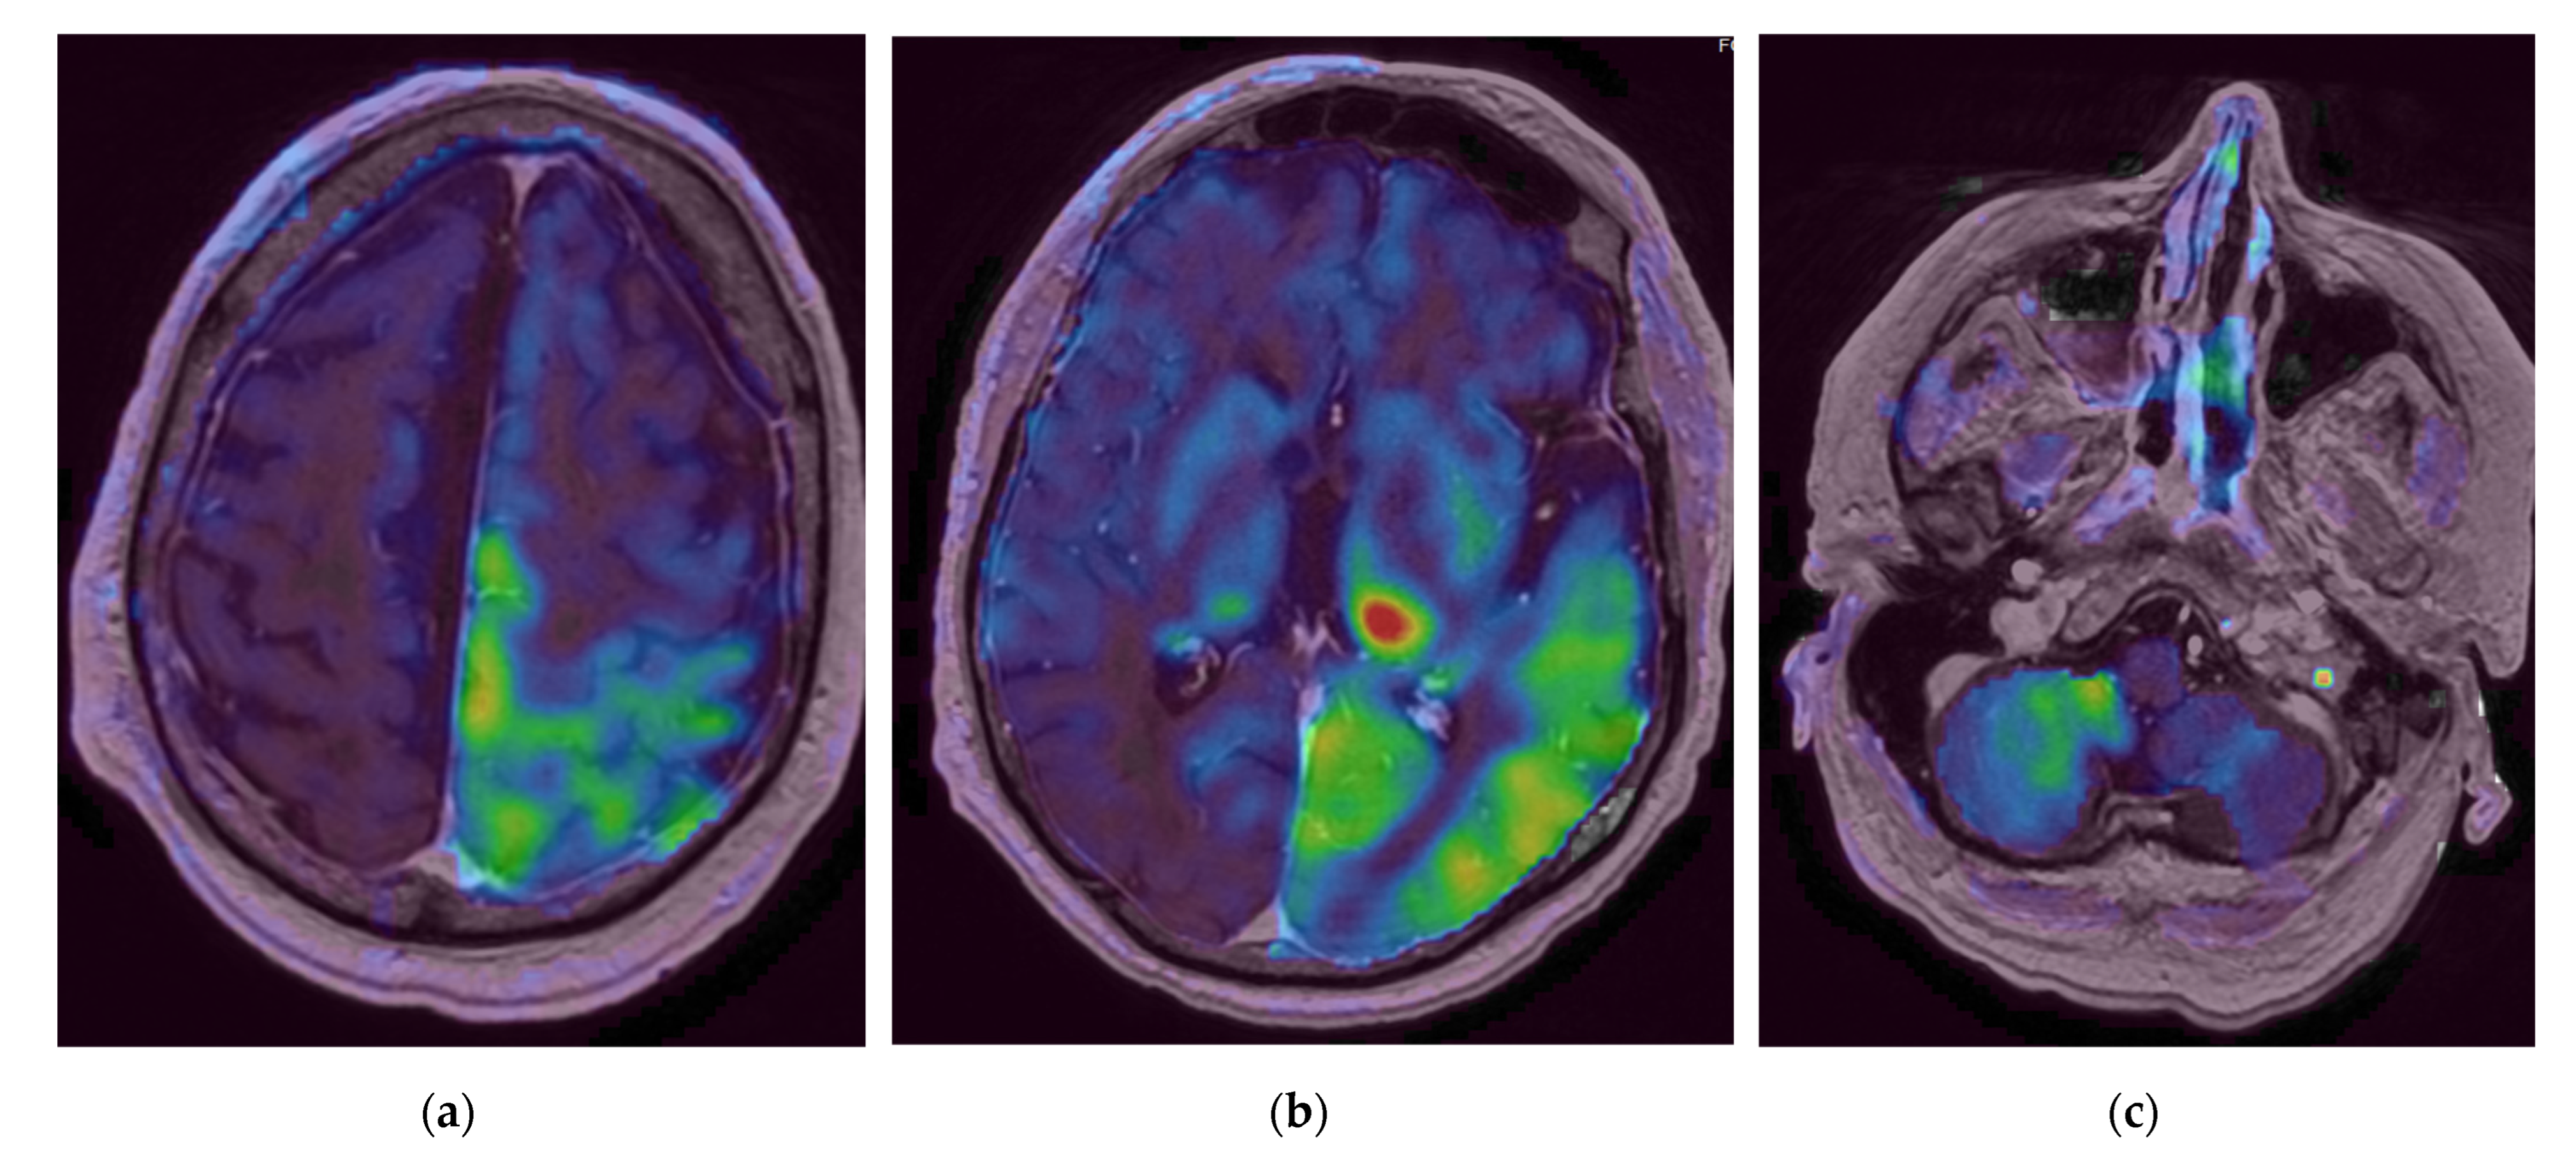

Figure 4.

Initial brain Magnetic Resonance Imaging (MRI) with arterial spin labelling (ASL) sequences. (a,b) Supratentorial acquisitions, (c) Infratentorial acquisition. We observe an increased perfusion (represented from green to red) within the left temporo-parietal-occipital, left thalamic and right cerebellar regions.

As for the pathophysiology of PRES, the increase of the cerebral blood flow (CBF) on the ASL sequences in the left temporo-parietal-occipital and the left thalamic reflected the increased cerebral perfusion in response to the excessive metabolic demands secondary to the seizure activity. These changes can lead to vasogenic and/or cytotoxic edema. Furthermore, the left thalamic increased DWI signal and the reduced ADC value in the pulvinar region was related to the status epilepticus. Indeed, the thalamus is involved in the transfer of information between the cortical and subcortical structures of critical activities, and potentially in their regulation and propagation [22]. The contralateral cerebellar increased CBF was due to the crossed cortico-thalamo-rubro-dentato-cerebellar fascicles, also called the crossed cerebellar diaschisis, represented in Figure 7 [23,24].